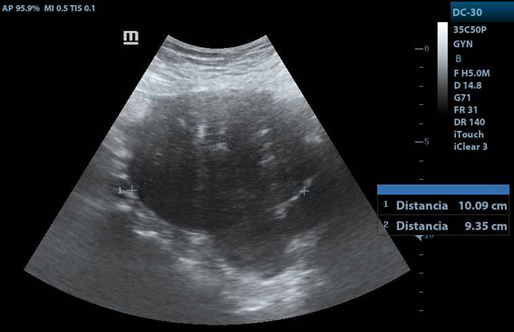

25-year-old patient, G2C1A1. FUM 05/15/2022, so-so. Two months before, she performed transvaginal post-abortion ultrasound (USG), finding a 6x6cm right adnexal tumor; Referred for new assessment, USG reporting a 9.5x7cm tumor, which is why she went to the University Hospital, accompanied by colicky pain in the right lower quadrant, in a scale of pain 6/10.

Transvaginal USG: uterus in AVF 4.5x5x3.3cm, LE 12.3mm. Right ovary: 4.8x3.6x3.7 cm vol. 34cc, with a tumor measuring 11.2x8.6cm, solid, with homogeneous and hypoechoic echotexture, with posterior acoustic shadow and Doppler flow uptake. Left ovary: 5x5x2.2cm vol. 19.6cc.

3. The characteristics of fibrothecomas by ultrasound are adnexal hypoechoic masses with a clear border and acoustic attenuation, as well as minimal Doppler flow signals. They are usually unilateral.

4. Combined with clinical information and CA125, ultrasound could be used as an imaging tool to improve the accuracy of preoperative diagnosis.

USG Transvaginal

1. Right adnexa, with heterogeneous image, hypoechoic mass, with clear border. with distance of 11.26X11X8.6cms.

1. Acoustic attenuation posterior a hypecoic mass en right adnexa.

1. Right adnexa with a deep flow of doppler color.